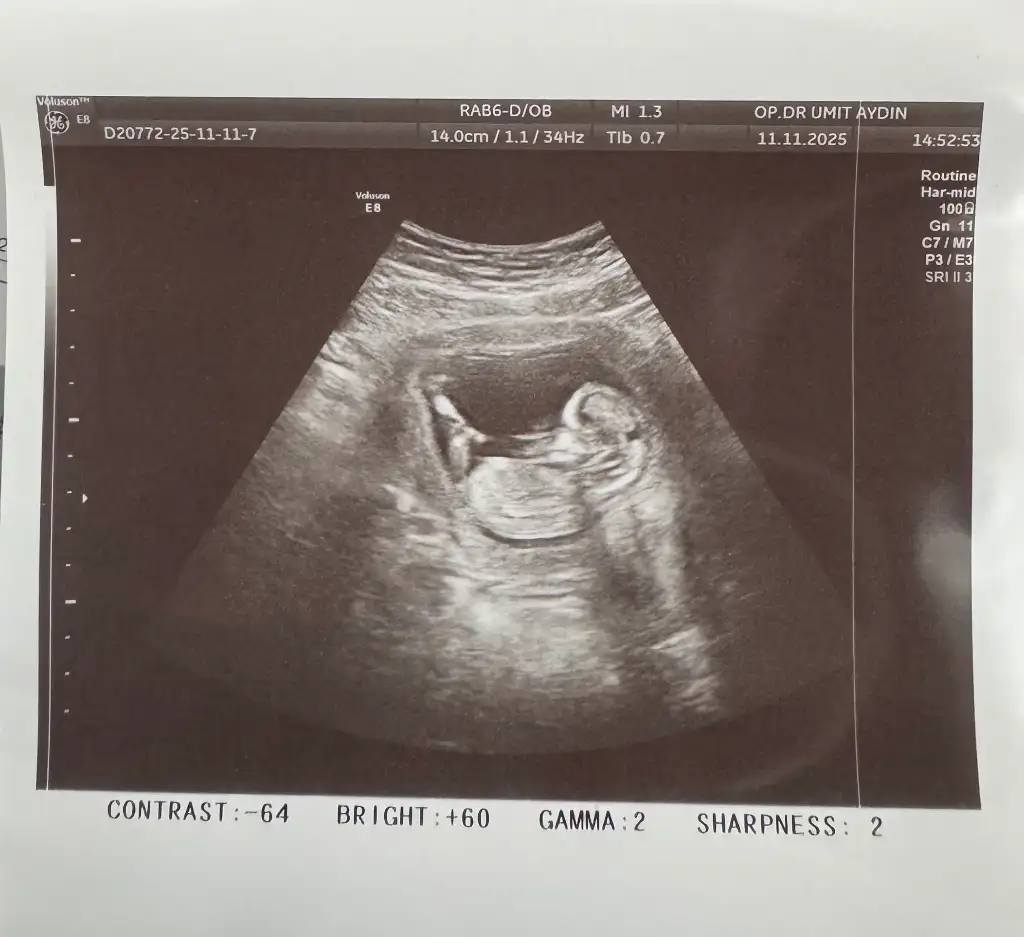

kızlaar bugün doktor kontrolüm vardı çok şükür herşey yolunda, fetal için kan verdik 1 haftaya çıkacakmış sonuç. Doktorum cinsiyette bi tahmini olduğunu söyledi ama organizasyon yapmak istediğimizi söyleyince fetali bekleyelim net olsun dedi. Ama eğlence olsun ultrason fotoğrafından tahmin eder misiniz sizce kız mı erkek mii

Eklentiler

• IMG_4552.webp

44,9 KB · Görüntüleme: 0

• IMG_4551.webp

23,3 KB · Görüntüleme: 0

• IMG_4547.webp

35,8 KB · Görüntüleme: 0